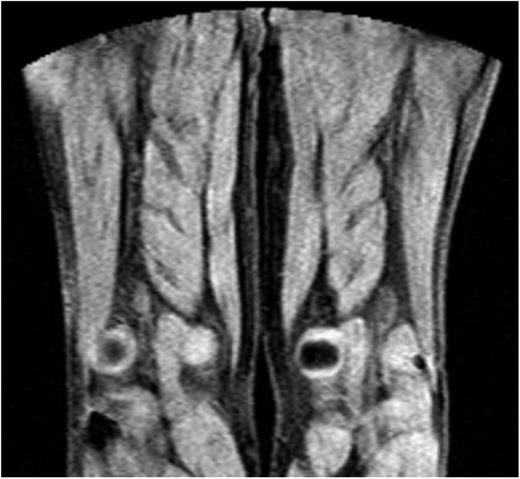

MRDTI was normal in all 42 patients of group 2, who had chronic thrombosis on CUS and no symptoms of acute recurrent DVT. Figure 2 depicts the normal MRDTI signal in a patient from study group 2 with asymptomatic residual thrombosis.

MDRTI image of a patient with ultrasonography-proven residual DVT but no acute recurrent thrombosis in the popliteal vein of the right leg. The scan did not indicate an abnormal MRDTI signal.